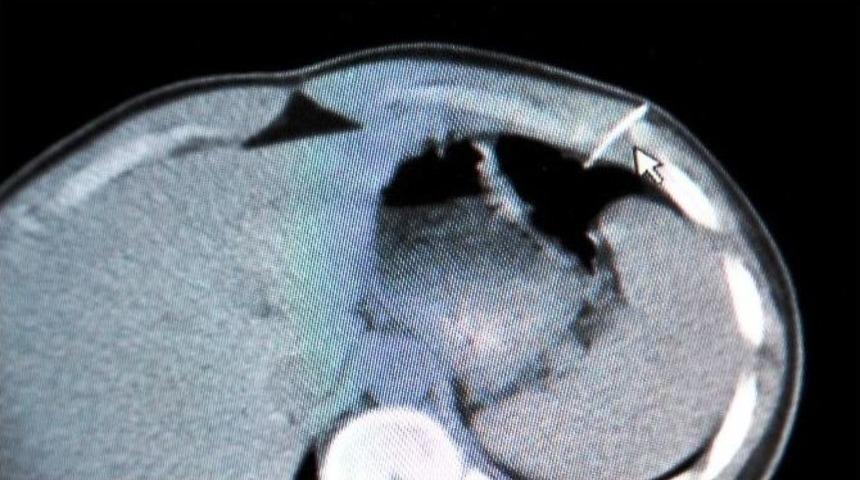

Kahramanmaraş’ın Elbistan ilçesinde gençler arasında enjektör iğnesi ile yapılan şaka, hastanede sona erdi. Şakalaşma esnasında göğsüne saplanan iğneyle hastaneye kaldırılan genç, yapılan başarılı operasyon sonucu sağlığına kavuştu.Gençler arasında yaşanan iğneli şaka, 17 yaşında bir gencin yaralanmasına neden oldu. Şakalaşırken batırılan enjektör iğnesi göğüsten sapıp bağırsak duvarına sağlandı. Göğüsten giren iğne kısa süren operasyonla çıkartılabildi.Özel Yaşam Hastanesi Genel Cerrahi Uzmanı Dr. Uğur Kılınç’a getirilen B.E. adlı genç, hemen ameliyat odasına alındı. Şakalaşırken göğse batırılan enjektör iğnesinin kaburgaların arasından bağırsak duvarına saplandığı belirlendi.Enjektör iğnesi operasyonla çıkarılırken, hasta kısa süre içerisinde taburcu edildi. Genel Cerrahi Uzmanı Dr. Uğur Kılınç, gençlerin bu tür şakalaşmalarda delici ve kesici alet kullanmalarının hayati tehlikelere yol açabildiğini belirterek, uyarıda bulundu. Kılınç, “Allah korusun bu tür kontrolsüz şakalaşmalar ölümle sonuçlanabiliyor. Gençlerimiz hayatının baharında basit bir şakayla canından olabiliyor. Bu olayda da gençler enjektörle birbirleriyle şakalaşmışlar ve B.E. adlı gencin göğsüne enjektör iğnesi saplanmış. Karın bölgesine gelen iğne bağırsak duvarına saplanıp kalmış. Bir anlık kontrolsüzlük, Allah göstermesin acı sonla bitebilir. Gençlerimiz dikkatli olmalı” diye konuştu.